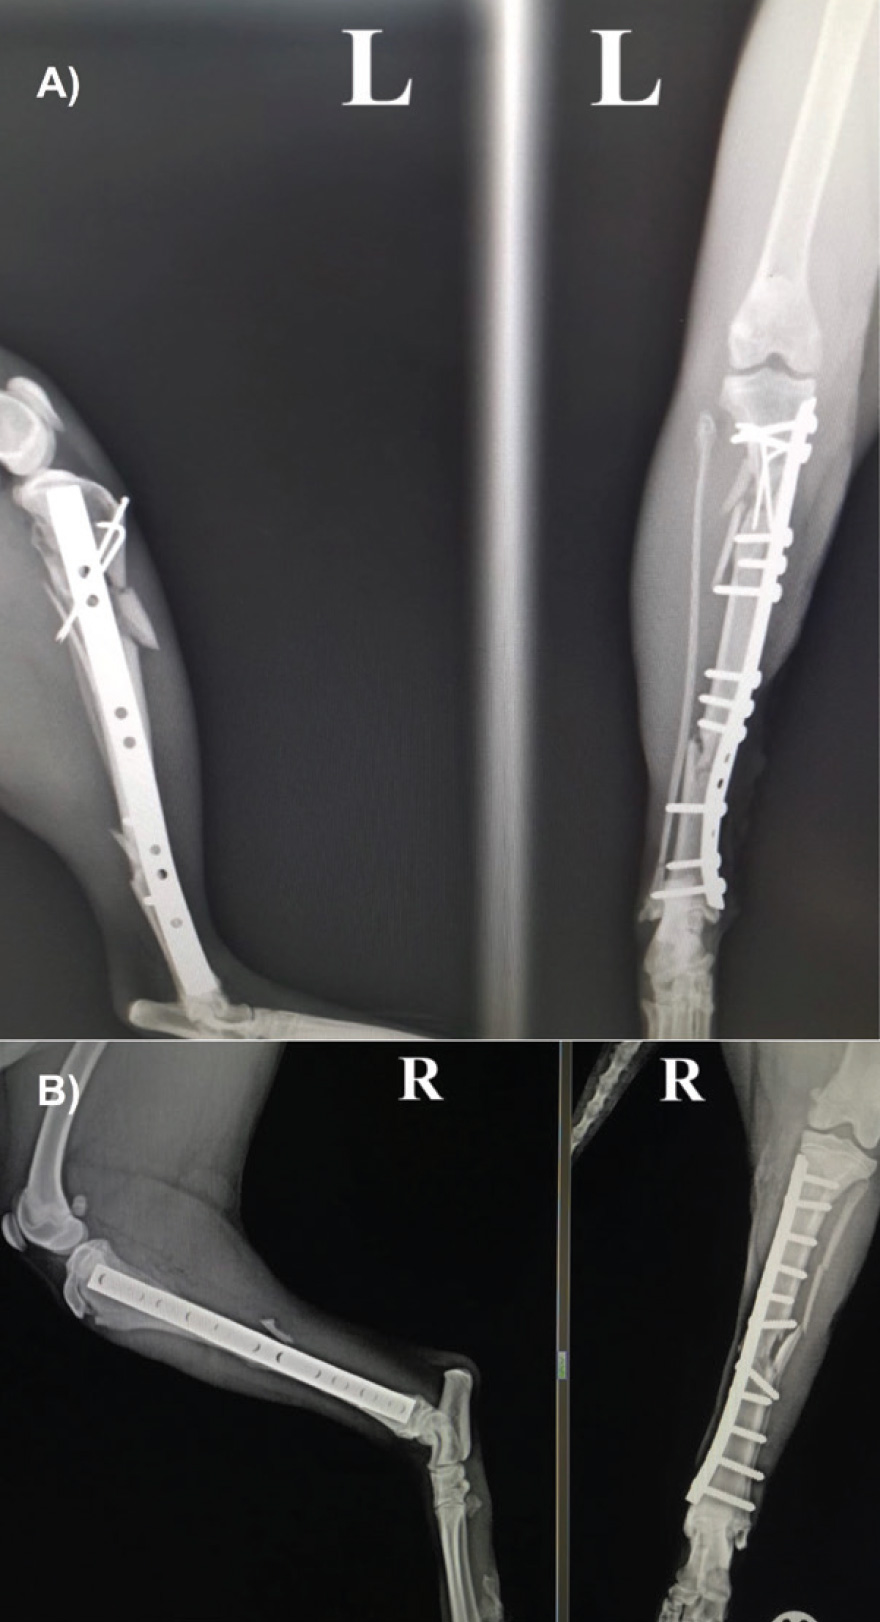

Linear or circular external fixators are common methods chosen to repair open fractures. Compared to internal fixation, this method allows a more biological approach by preserving the local soft tissues and avoiding vascular compromise, which is particularly important when treating open fractures. They allow easy access to the wound bed to evaluate soft tissue healing and make changes in open wound management if needed. They also stand out for their versatility, as they can be successfully used to temporarily immobilise a joint if necessary (Figure 6). They can also be removed once the fracture healing has completed, without any need for a second surgical procedure. Despite the clear advantages of external fixation, some fractures, such as highly comminuted or articular fractures, may require stronger methods of internal fixation (Figure 7). In these cases, a second surgical procedure to remove implants may be required once fracture healing occurs to prevent implant-associated infections.

Figure 7: A) Fracture repair in patient of Figure 1A using internal fixation. B) Fracture repair of an open fracture using internal fixation in another feline patient.